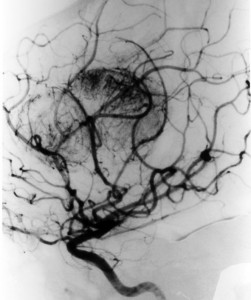

前頭葉にできた悪性黒色腫 malignant melanomaの脳血管撮影像です。腫瘍は強く濃染して大きな導出静脈があります。開頭手術で腫瘍を摘出しようとするとものすごく出血しました。局所放射線治療やダカルバジンの化学療法を行ないましたが全く無効でした。